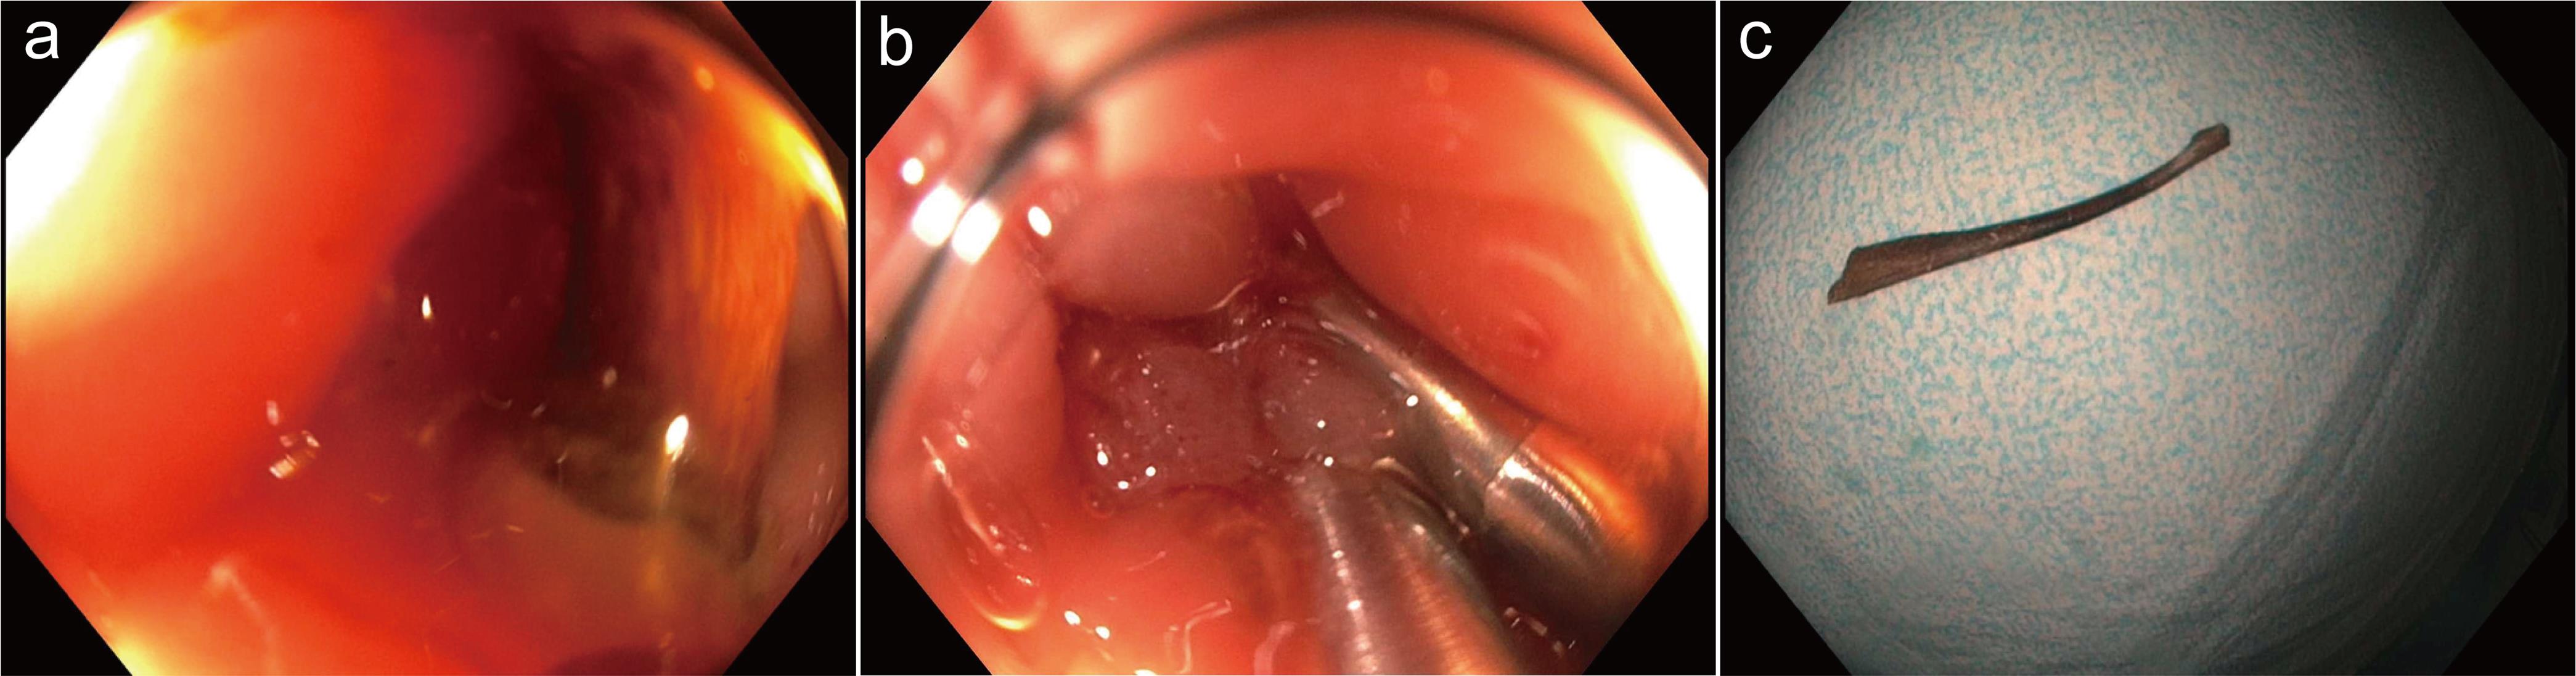

A colonoscopy was performed with the CFHQ 190L Olympus colonoscope to the level of the cecum without difficulty. A large foreign body, which appeared to be a chicken bone with surrounding edematous thick mucosal folds, was found perforating through the colonic wall in the mid-sigmoid colon and wedged into the opposing colonic wall (Fig. 2a). The end wedged into the opposing colonic wall was teased out with the Raptor grasping device forceps and the large radial jaw biopsy forceps. A 13 mm snare was placed around the foreign body, and it was removed with gentle traction of the colonoscope in a retrograde fashion. The colonoscope was reinserted, and two clips were placed at the site of the perforation (Fig. 2b). A nearby 3 mm colonic polyp was excised with cold biopsy forceps as well. Multiple medium-mouthed diverticula were found throughout the entire colon. Pathologic review revealed an animal bone 4.2 cm in length with a diameter ranging from 0.2–0.4 cm (Fig. 2c).

Images obtained at the colonoscopy.

Fig. 2  Images obtained at the colonoscopy.

(a) Colonoscopy image: Foreign body wedged into the sigmoid colon wall. (b) Colonoscopy image: Endoscopic clips were placed at the site of the foreign body after removal. c. Image of chicken bone 4.2 cm. in size after removal.